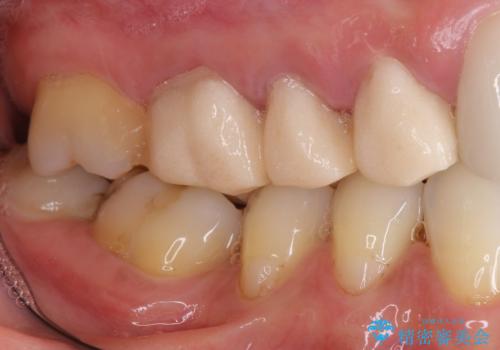

- 他院で仮歯まで入れたものの違和感があることを主訴に来院された患者様です。

違和感があると訴えたにも関わらずそのまま被せようとする他院に不安を感じ、通院をやめてしまったとのことでした。

丁寧にう蝕除去と再根管治療を行い症状の改善を確認したのち、セラミッククラウン及びセラミックインレーによる補綴を行いました。